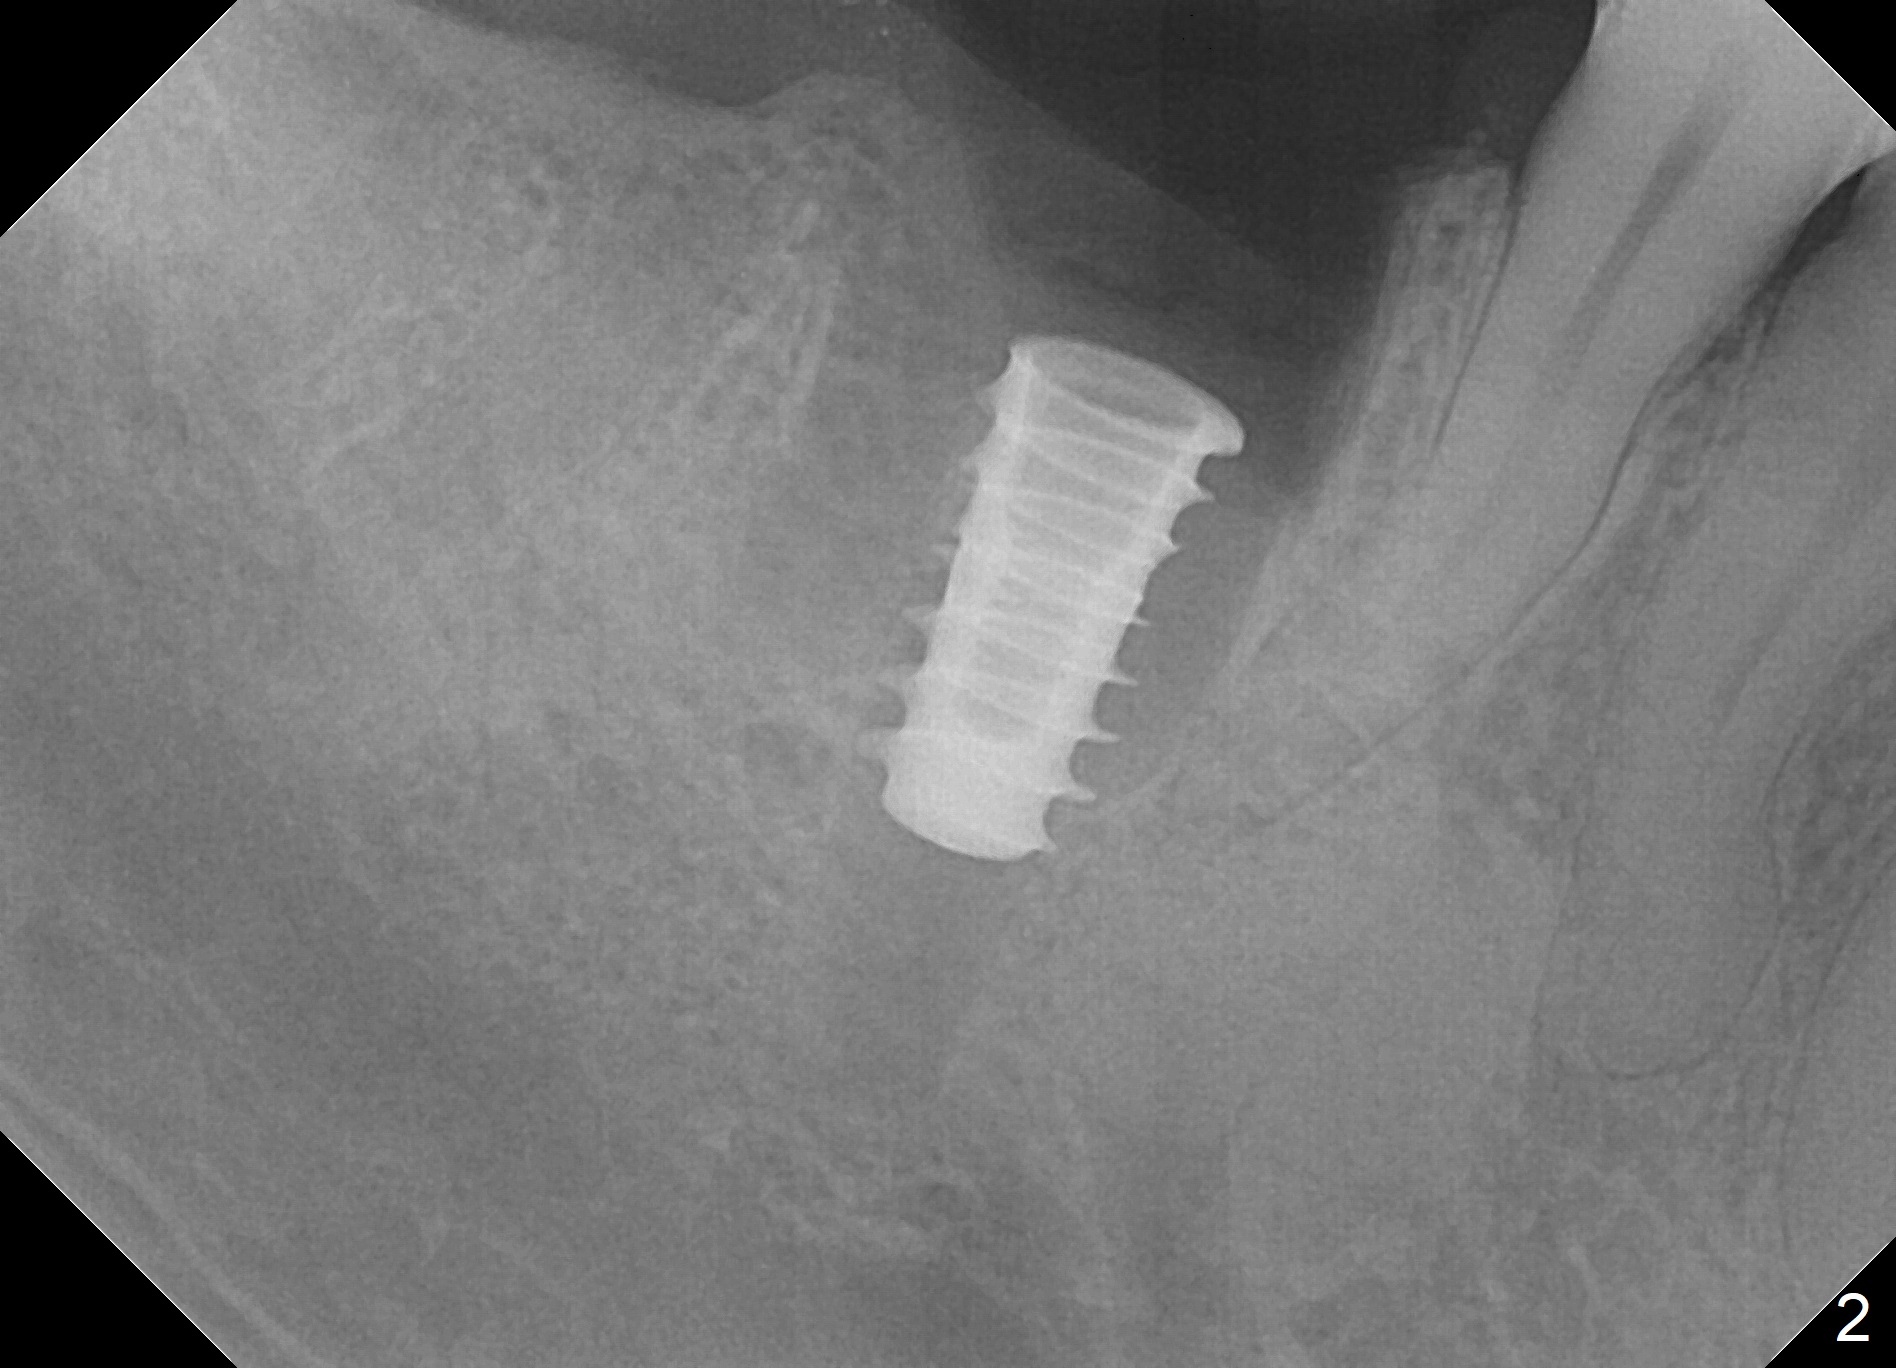

Extraction is difficult due to hard bone and brittle, curved roots of the tooth #30; initial depth in the septum is 14 mm (gingival level, Fig.1). Then the depth increases to 17 mm; with sequential osteotomy using 2.8 mm to 4.8 mm Magic Drills (MD), a 5x9 mm dummy implant is placed incompletely due to hard bone (Fig.2). After use of 5.3 mm MD for ~ 15 mm, the dummy implant is placed to the depth (Fig.3). The definitive IBS implant (5x13 mm) is placed with 50 Ncm; a 6.5x5.7(4) mm abutment is placed with allograft filling the gap (* and arrow).